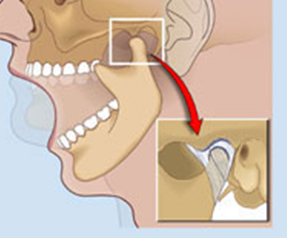

TEMPOROMANDIBULAR EKLEM

DETAYLI BİLGİ